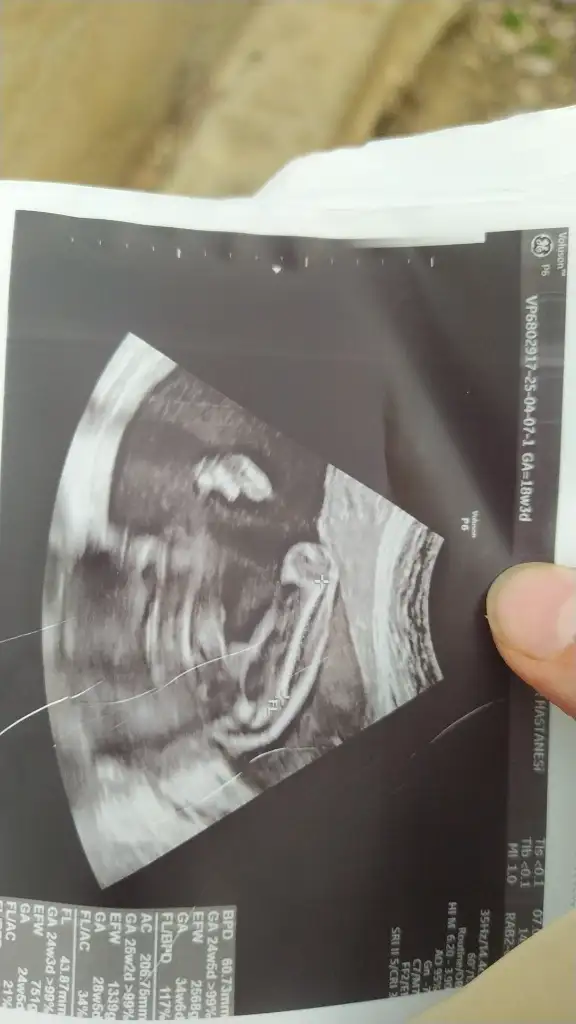

Sizin ultrason fotografinizda birinci bacak arası resmini erkeğe ikinci bacak arası resmini de kıza benzettim 🙈 daha tecrübeli arkadaşlar yorum yapabilir 😍birincisinde bariz çıkıntı var gibi duruyor ama ikincisinde birşey gözükmüyor.

• IMG_20250407_163039_632.webp

IMG_20250407_163039_632.webp

21,7 KB · Görüntüleme: 39